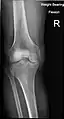

X-ray

- Knee X-ray

- Knee X-ray (weight bearing)

- Knee X-ray (weight bearing, flexion)